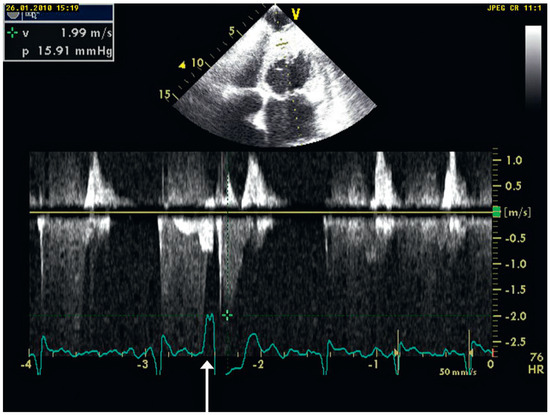

Interesting Images

Giant Apical Aneurysm without Coronary Artery Disease

by Stéphane Chevallier and Jean-Christophe Stauffer

Abstract

A 66-year-old patient with some years’ history of apical hypertrophic cardiomyopathy treated by beta-blockers attended for follow-up echocardiography [...] Full article

Figure 1